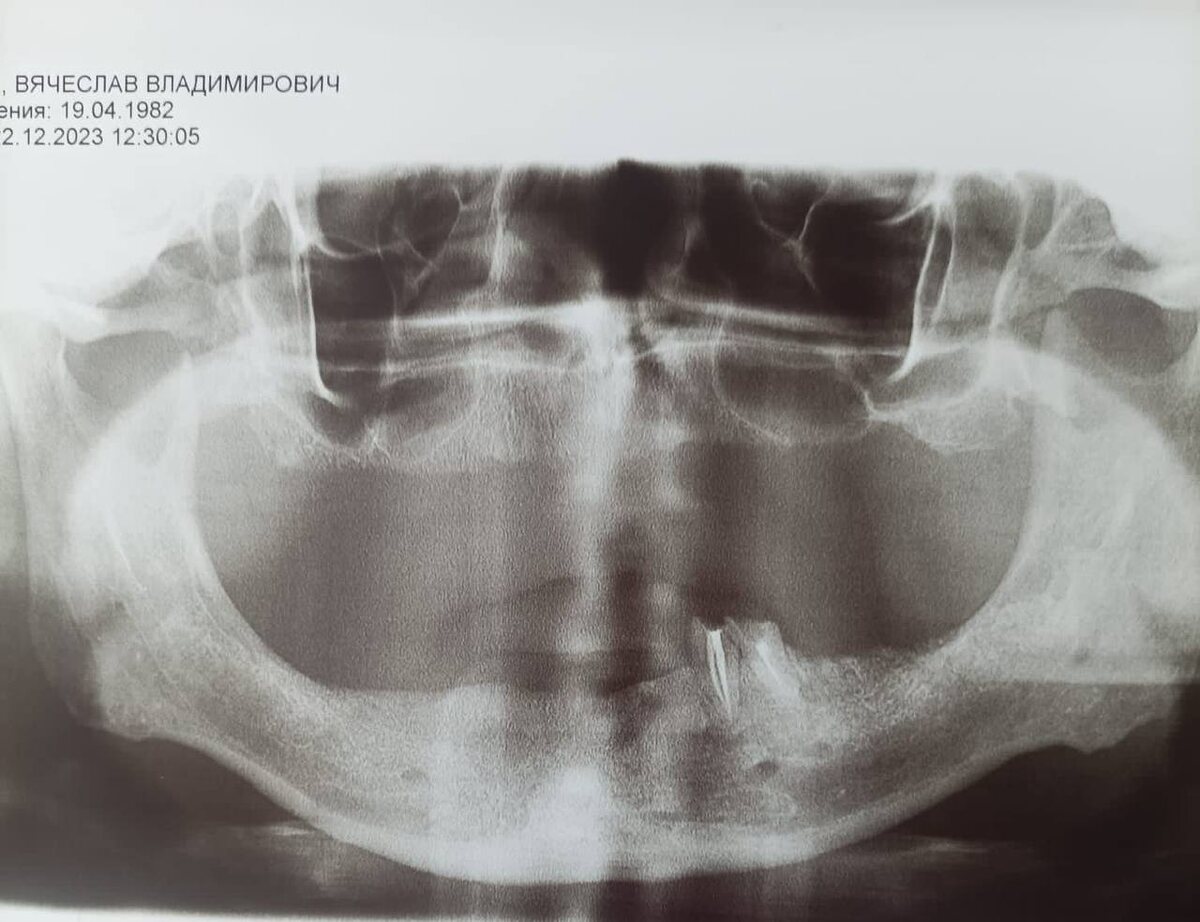

Снимок "до". На нижней челюсти только два зуба (корни).

В январе 2024 года Вячеслав обратился к нам за помощью. Его ситуация была сложной: на нижней челюсти оставались только два корня, а все остальные зубы отсутствовали. От съемных протезов он отказался, выбрав более современное решение – имплантацию зубов в Китае.

Однако долгий период без зубов привел к атрофии кости, что осложняло процесс. Мы составили четкий план: